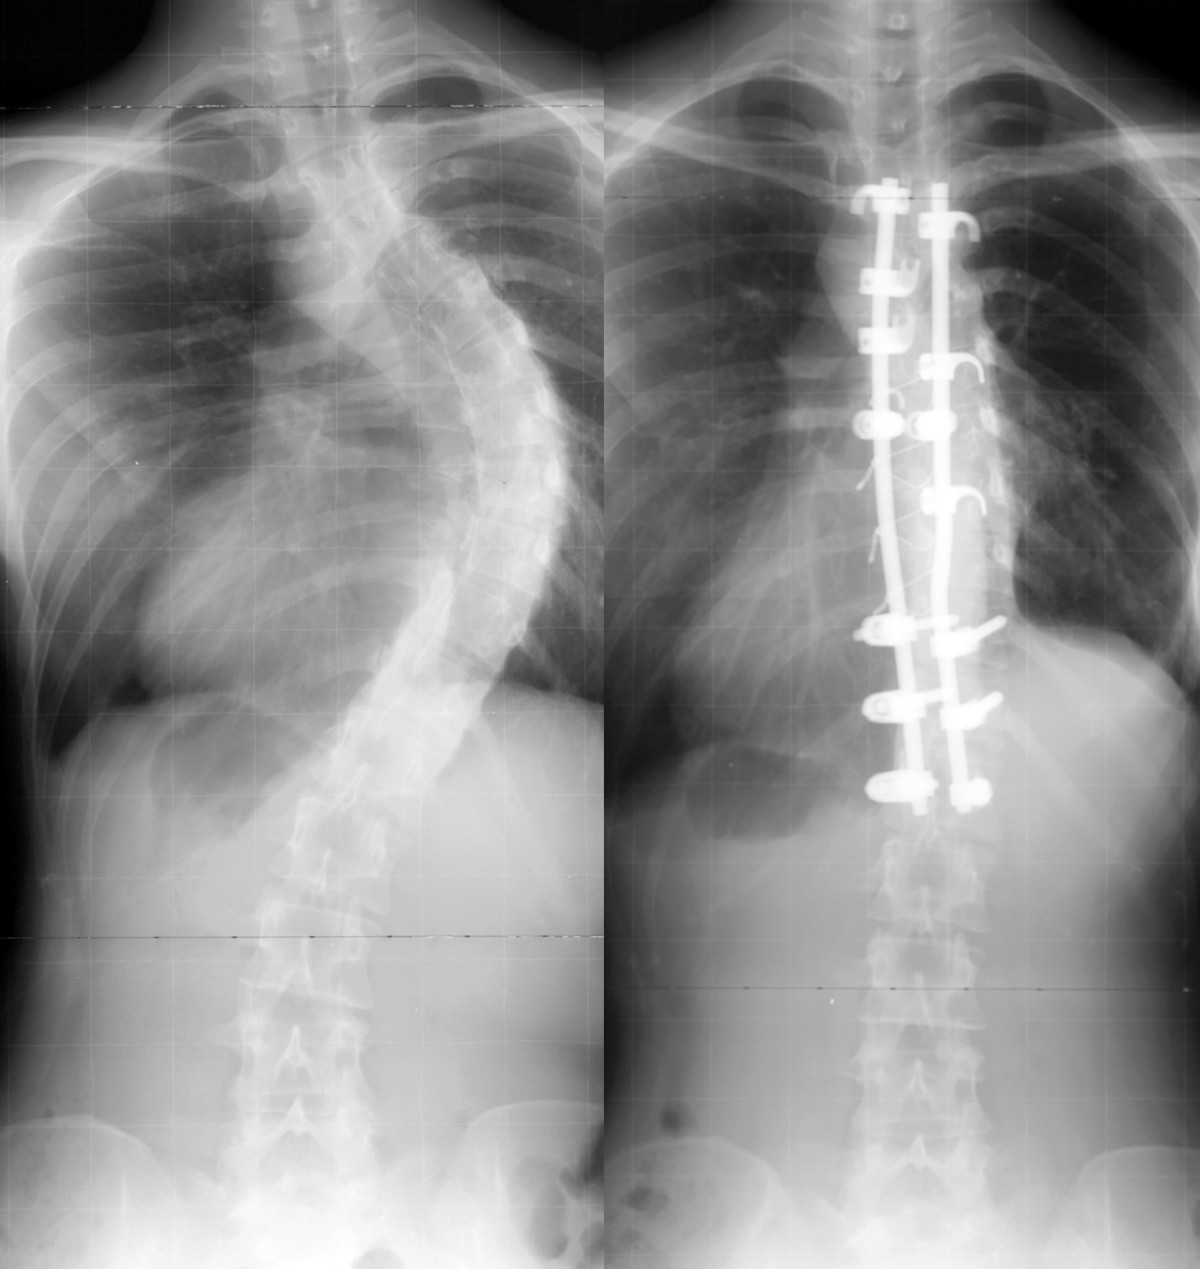

Surgery to correct scoliosis involves placing one or two metal rods stabilized by hooks and screws along the spine in an effort to prevent further curvature. Posterior fusion with instrumentation has been a standard of the surgical treatment for scoliosis since first introduced by paul harrington. The traditional way to treat scoliosis involves periods of observation, bracing (though this is generally for adolescent patients whose spines are not fully developed) and then surgery if the curve progresses much past 40 degrees.

Posterior fusion with instrumentation has been a standard of the surgical treatment for scoliosis since first introduced by paul harrington. The standard surgical treatment for scoliosis is a spinal fusion that corrects spinal deformity curves. With any of the surgical options, maximizing nutrition and medical status prior to surgery are critical to minimize complications.

When the angle exceeds 45 to 50 degrees, surgical correction may be necessary. This procedure fuses together vertebrae to stop progression of scoliotic curves. The purpose of the surgery is to fuse the curved vertebrae of the spine into one large bone.